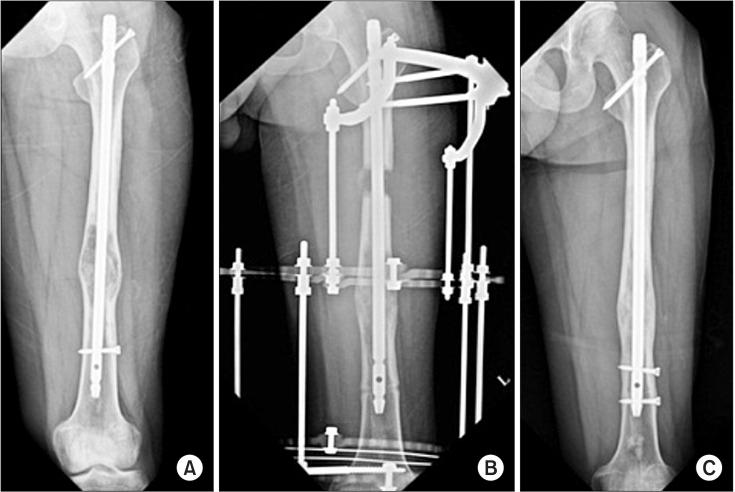

Diaphyseal unicameral bone cysts of the long bone are generally known to originate near the growth plate and migrate from the metaphysis to the diaphysis during skeletal growth. In the case of unicameral bone cysts of diaphyseal origin, recurrence at the same location is extremely rare. We report a case of recurrence of a unicameral bone cyst in the diaphysis of the femur that developed 8 years after treatment with curettage and bone grafting. We performed bone grafting and lengthening of the affected femur with an application of the Ilizarov apparatus over an intramedullary nail to treat the cystic lesion and limb length discrepancy simultaneously.

长骨骨干单房性骨囊肿通常起源于生长板附近,并在骨骼生长过程中从干骺端向骨干迁移。对于骨干起源的单房性骨囊肿,在同一部位复发极为罕见。我们报告一例股骨骨干单房性骨囊肿在刮除植骨治疗8年后复发的病例。我们应用Ilizarov装置在髓内钉上对患侧股骨进行植骨和延长,以同时治疗囊性病变和肢体长度差异。